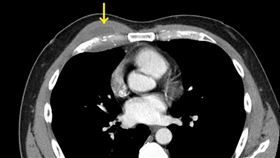

愛吃半熟蛋!男胸口冒腫塊裡面全是膿

55歲賴先生一向身體健康,沒慢性病也幾乎不感冒,但平...